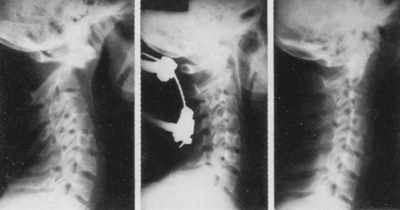

Больная Г., 25 лет. В автоаварии за 2 мес до поступления

получила травму шейного отдела позвоночника - перелом основания зубовидного

отростка С2-позвонка. На первичных рентгенограммах перелом был без смещения

и не был диагностирован. Больная 3 нед ходила в мягком воротнике Шанца, затем

в связи с сохранением болевого синдрома в травмпункте спустя почти 2 мес были

выполнены повторные рентгенограммы, на которых выявлен полный трансдентальный

вывих атланта (рис. 3). При поступлении в ЦИТО органической неврологической

симптоматики не выявлялось. В ортопедическом статусе отмечалось выраженное ограничение

движений в шее. Больной был наложен галоаппарат с дополнительной спицей, проведенной

через остистый отросток С2-позвонка. Осуществлено полное вправление вывиха (рис.

3). Через 4 мес диагностирована консолидация в правильном положении.

Рис. 3. Застарелый перелом зубовидного отростка

С2. вправление в галоаппарате, сращение перелома в правильном положении. |